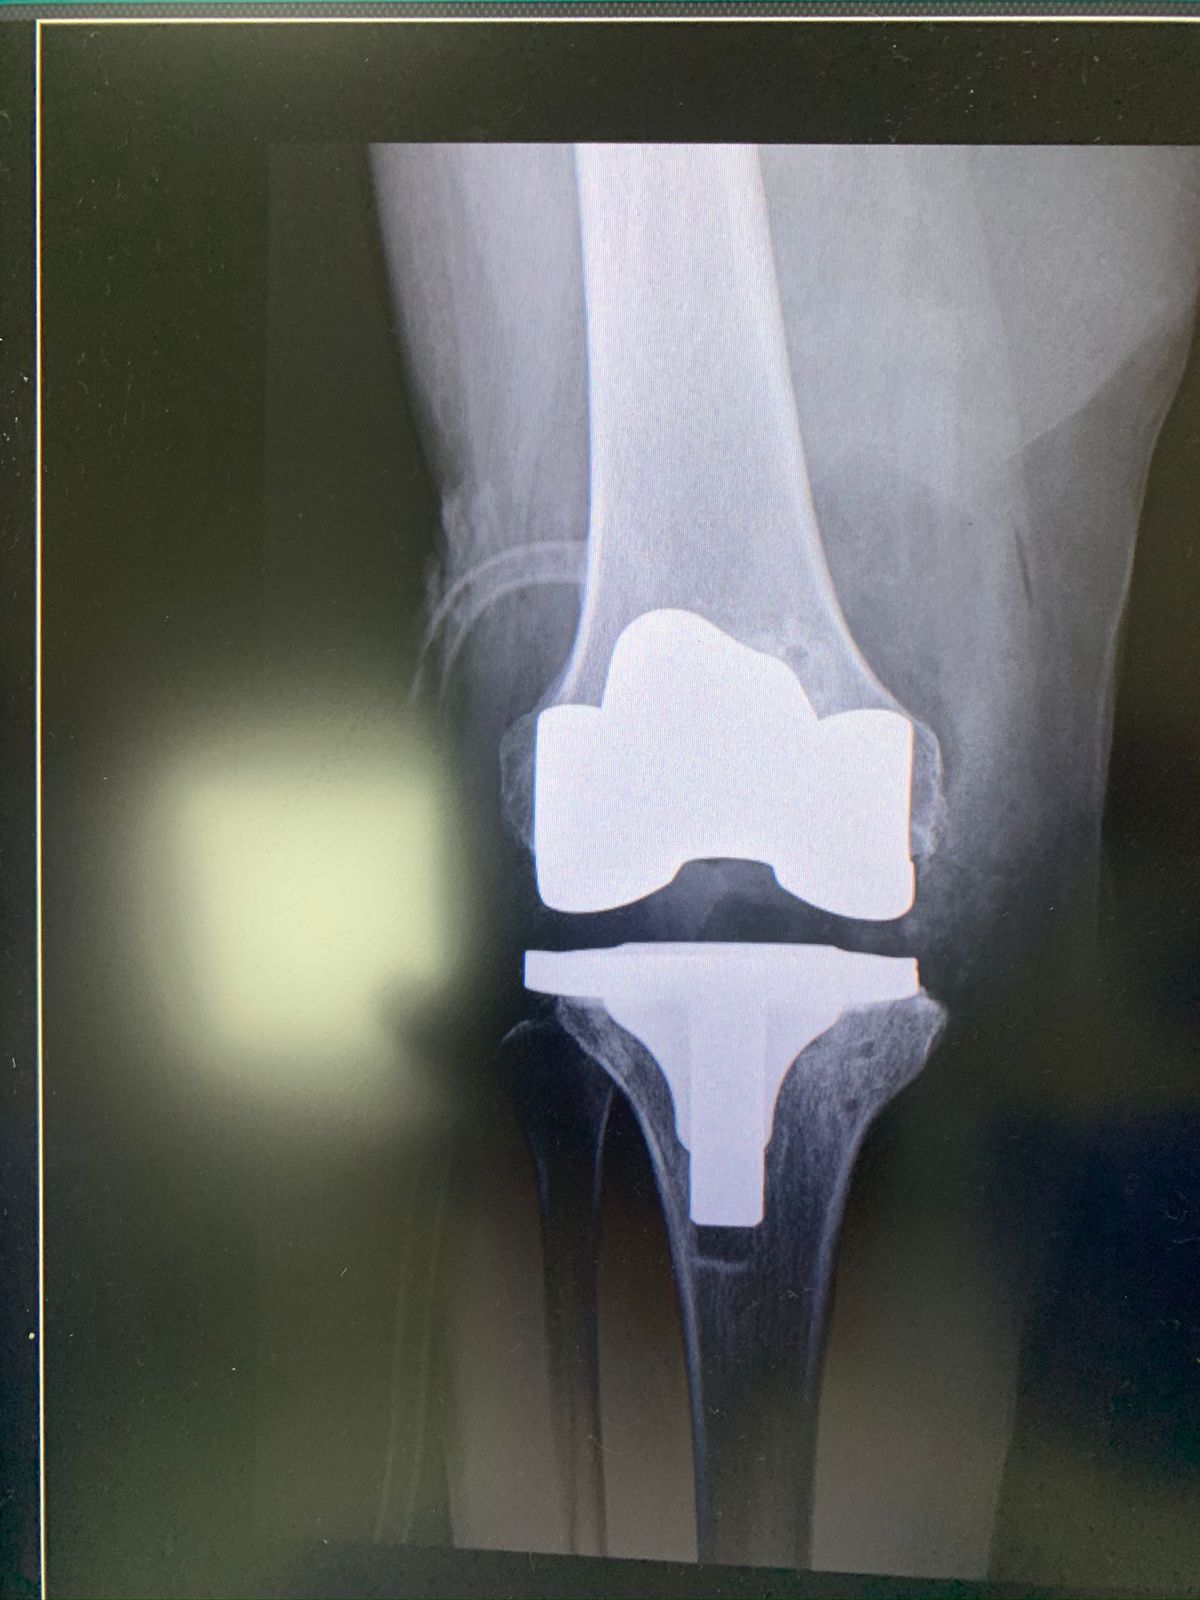

• Prótesis de rodilla

Los dolores en la rodilla pueden dividirse en dos tipos: 1.- Los agudos o de forma inmediata, ocasionados por un accidente, golpe directo, torcedura o realizar algún deporte. Muchas veces el diagnóstico consiste en descartar o confirmar alguna lesión de ligamentos, tendones o incluso fracturas. 2.- Los dolores crónicos de la rodilla pueden durar muchos años y pueden ser ocasionados por enfermedades degenerativas o secundarios a lesiones que no se atendieron en el momento, algunos ejemplos de estas lesiones son la hoffitis, lesiones de meniscos, lesiones de ligamentos cruzados, desgastes articulares, entre otros El tratamiento dependerá del tipo de dolor